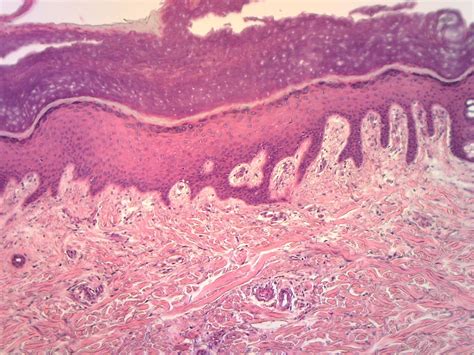

Histological Features of Stratified Squamous Epithelium Keratinized

The histological features of stratified squamous epithelium keratinized can be observed through microscopic examination. Key features include:

Layer Cell Shape Characteristics

Basal Layer Cuboidal or Columnar Actively dividing cells

Spinous Layer Flattened with Spines Interconnected cells

Granular Layer Flattened with Granules Contains keratin granules

Cornified Layer Flattened and Keratinized Dead, keratinized cells

These histological features provide valuable insights into the structure and function of stratified squamous epithelium keratinized, aiding in the diagnosis and management of various conditions.